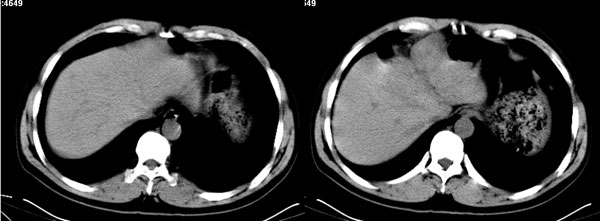

李**,男,46岁,便血1天入院,慢性贫血貌,腹平、软,剑突下压痛,肠鸣音稍活跃,hb大于1g/l,胃镜:慢性浅表性胃炎,b超:1肝内多发性占位 2腹腔内囊性肿块 ,肝内圆形影平扫ct值42.9,动脉期48.6,静脉期58.2,延迟期62.2

影像学表现:1 腹腔前中部、胰腺前方囊实性病灶(个人认为确定有否实性成分存在这是关键,涉及到鉴别诊断,如果是口服阳性造影剂则可明确左侧是不是小肠了),囊性部分囊壁不均,实性部分有强化,与小肠关系较密切,局部小肠受推移;与胰头、胃后壁均有脂肪间隙存在;2 胰腺无异常改变,胰周无渗出;3肝后段包膜下2个小圆形低密度灶,从图像和楼主提供的ct值来看有轻度强化,灶周无片状强化,不似单纯囊肿及肝癌、炎性病变表现;4 腹膜后及腹腔内无淋巴结肿大。

胰腺边界清晰,胰周筋膜不厚,胰周脂肪密度无明显增高;其前方囊实性病灶,边界清晰,增强后实性部分轻度强化;肝内多发边界清晰低密度影,增强后无明显强化(平扫ct值42.9,动脉期48.6,静脉期58.2,延迟期62.2)。

原因:胰头前方,前上腹部巨大囊实性肿物,与小肠关系密切,与胰头及胃壁之间脂肪间隙存在,囊壁不均匀,部分强化,占位效应明显,小肠上段扩张,十二指肠及胃腔内大量食物存留,说明上消化道有部分梗阻。因此,考虑来源于肠道的肿瘤。再结合其病史及肝内改变,这样考虑更有道理。